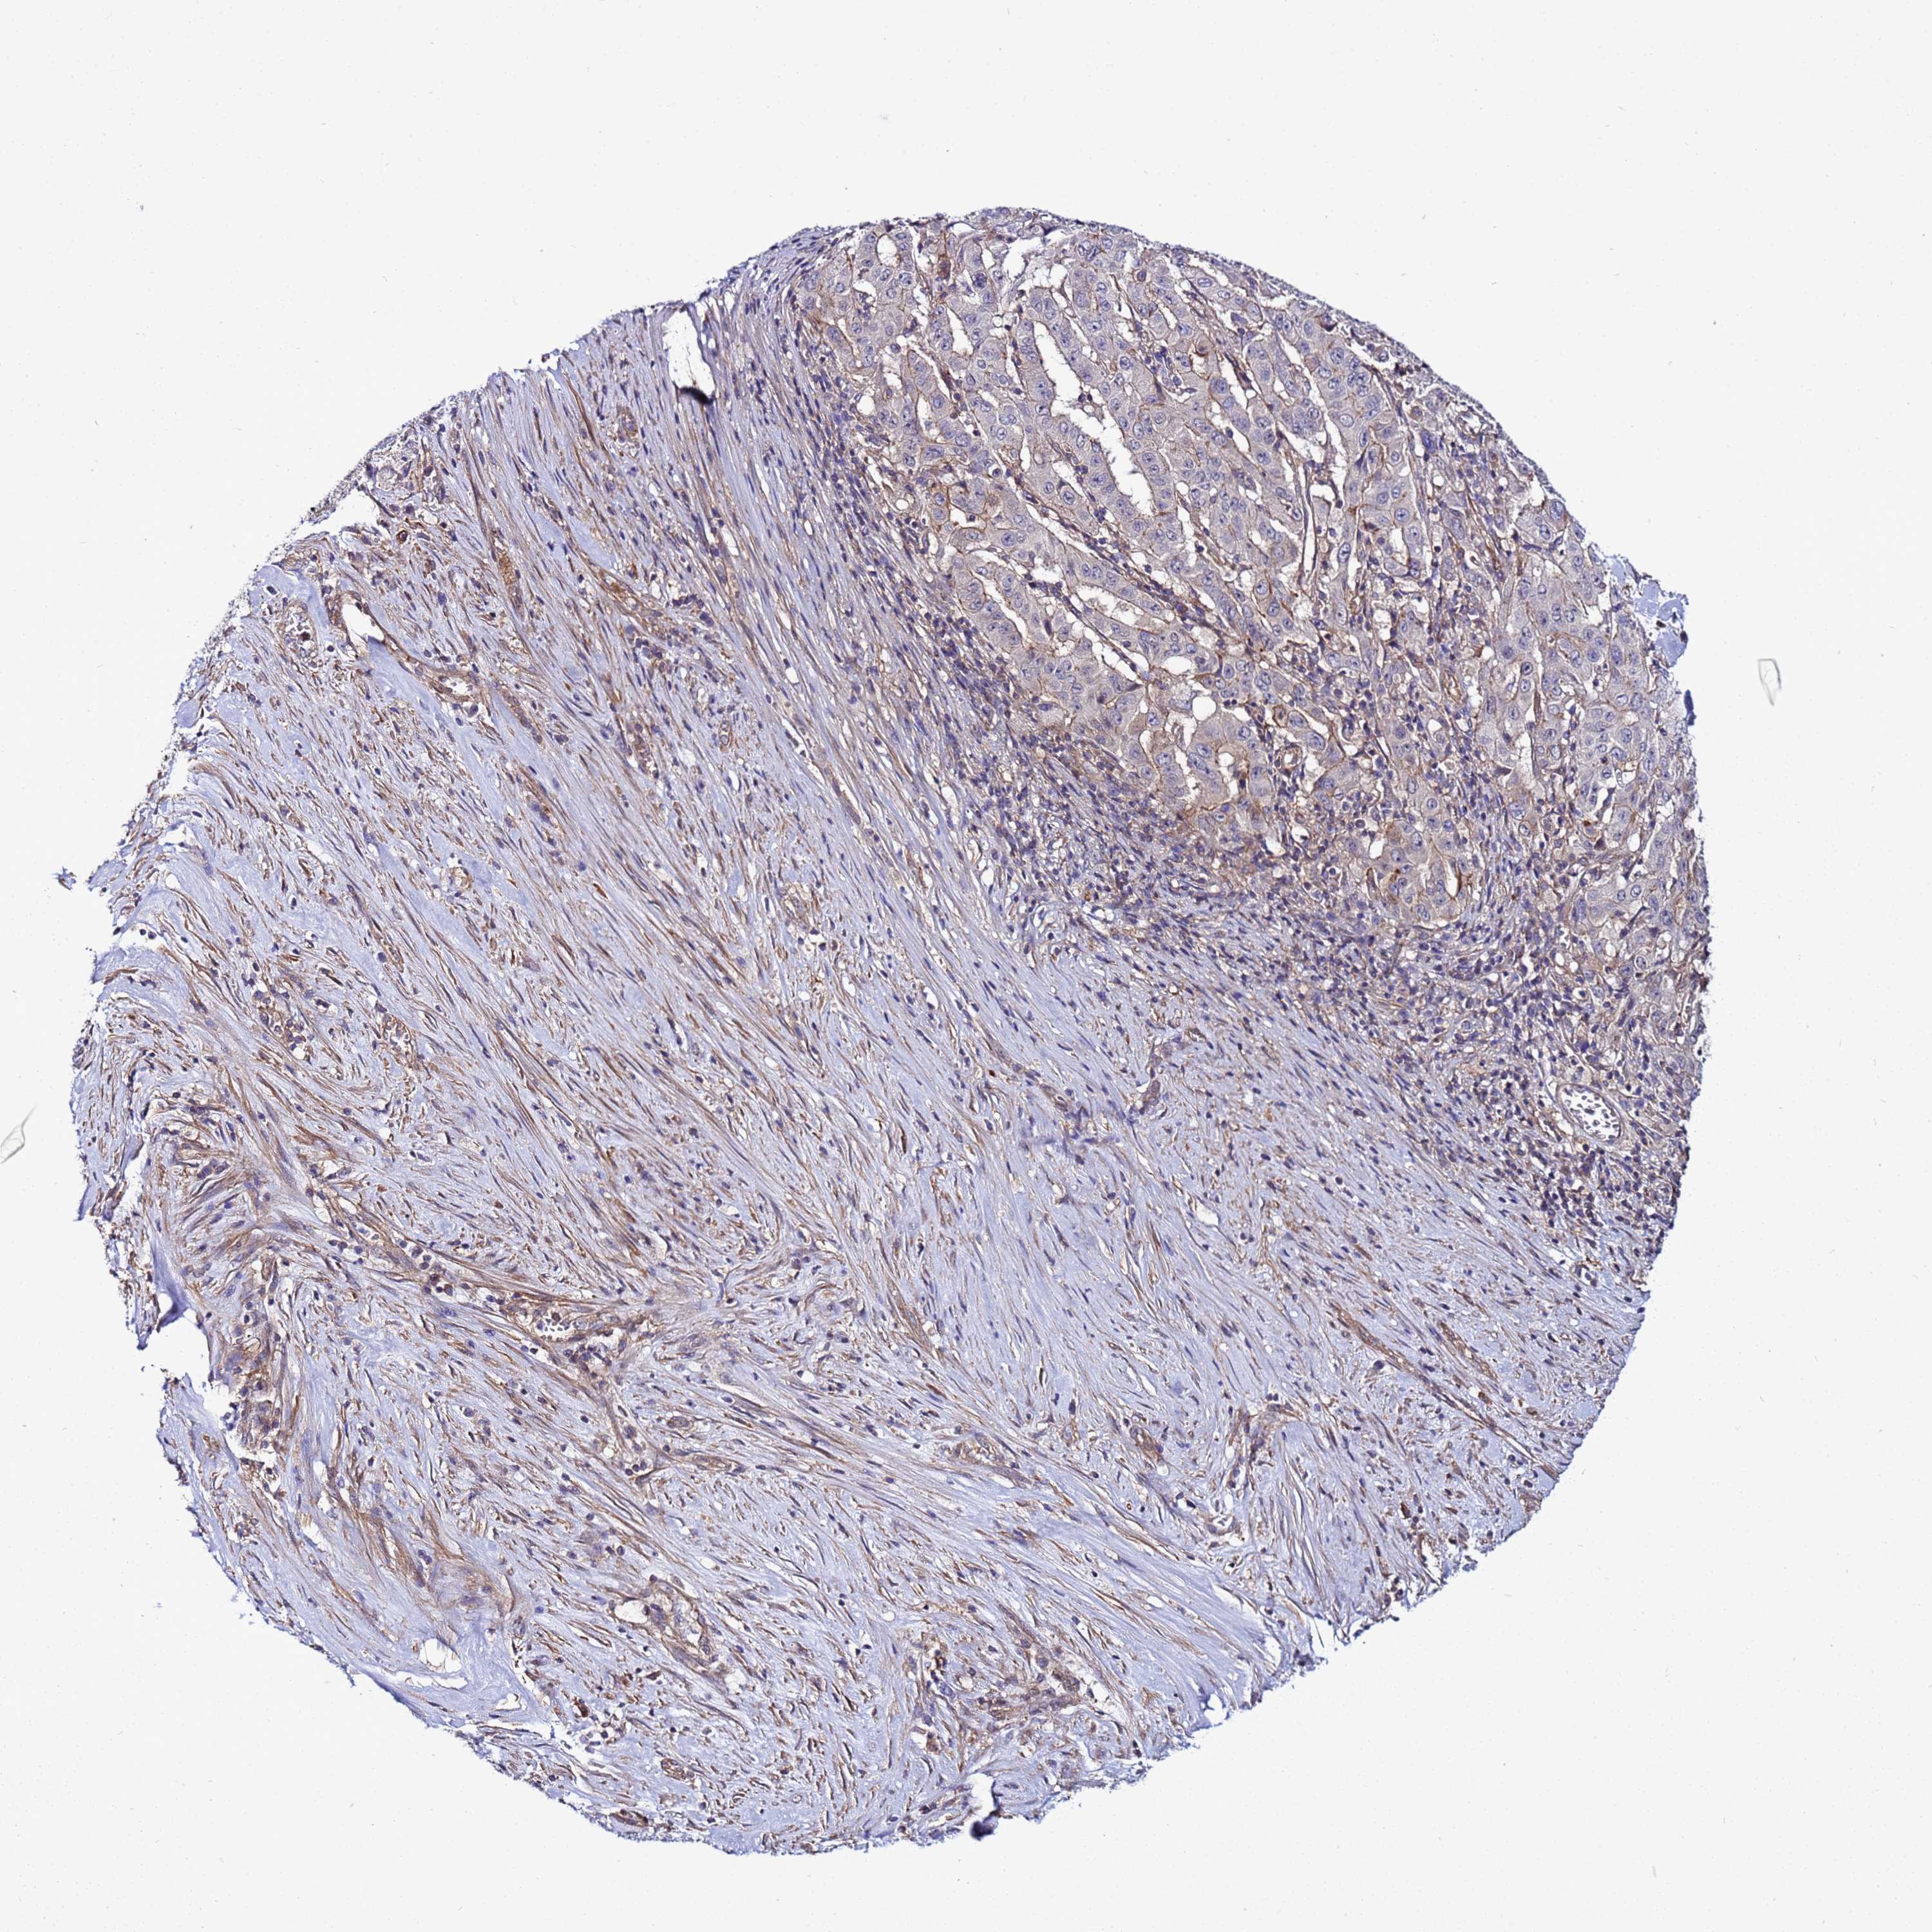

PANCREATIC CANCER - Protein expressioni

A mouse-over function shows sample information and annotation data. Click on an image to view it in a full screen mode. Samples can be filtered based on level of antibody staining by selecting one or several of the following categories: high, medium, low and not detected. The assay and annotation is described here.

Note that samples used for immunohistochemistry by the Human Protein Atlas do not correspond to samples in the TCGA dataset.

Antibody stainingi

Antibody staining in the annotated cell types in the current human tissue is reported as not detected, low, medium, or high, based on conventional immunohistochemistry profiling in selected tissues. This score is based on the combination of the staining intensity and fraction of stained cells.

Each image is clickable and will lead to virtual microscopy that enables deeper exploration of all samples and also displays staining intensity scores, fraction scores and subcellular localization as well as patient and tissue information for each sample.

Antibody HPA038623

Staining

High

Medium

Low

Not detected

Intensity

Strong

Moderate

Weak

Negative

Quantity

>75%

75%-25%

<25%

None

Location

Nuclear

Cytoplasmic/membranous

Cytoplasmic/membranous,nuclear

Adenocarcinoma, NOS